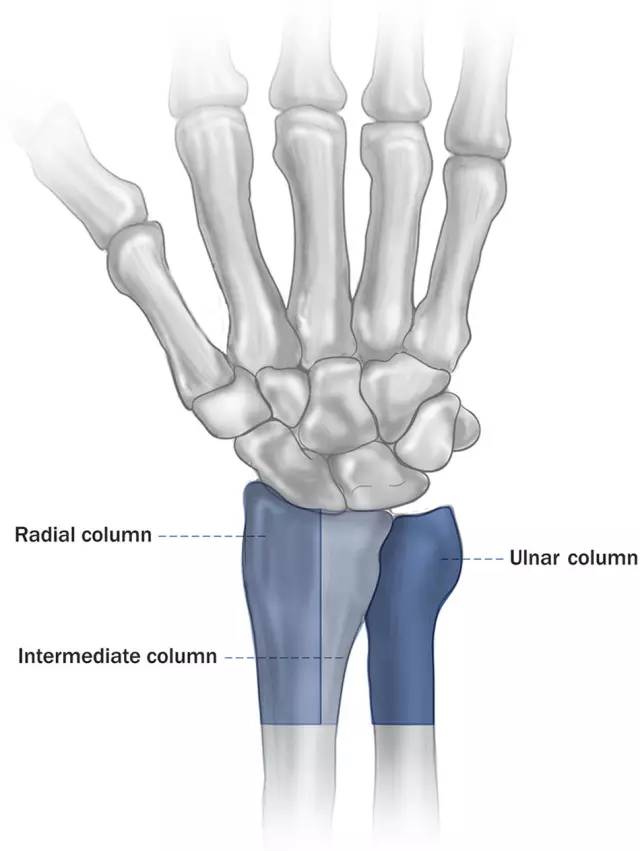

以尺桡骨远端的生物力学和解剖学特征为基础提出的三柱理论,是 2.4 mm 钢板系统研发和临床应用的基础。

图 1. 尺桡骨远端的三柱理论

桡侧柱为桡骨远端外侧半,包括舟骨窝和桡骨茎突,对于桡侧的腕骨具有支撑作用,一些稳定腕关节的韧带也起自于此。

中柱为桡骨远端的内侧半,包括关节面的月状窝(与月骨相关节)和乙状切迹(与尺骨远端相关节)。通常情况下负荷,来自月骨的负荷经由月骨窝传递到桡骨。

尺侧柱包括尺骨远端、三角纤维软骨和下尺桡关节,承载来自尺侧腕骨以及下尺桡关节的负荷,具有稳定作用。